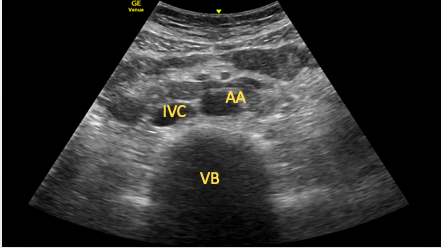

Subcostal Short-Axis View of the Inferior Vena Cava and Aorta

The SC IVC or aortic short-axis view should be obtained and a 90° clockwise rotation performed. The transducer is then tilted to point caudally until the IVC and aorta are seen in transverse section (Figure 15). This view can be useful in identifying aortic dissections or aneurysms (as part of a full aortic scan).15

Figure 15. Transverse view of the aorta and inferior vena cava.

AA=abdominal aorta, IVC=inferior vena cava, VB=vertebral body